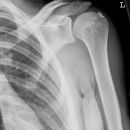

Schulterluxation